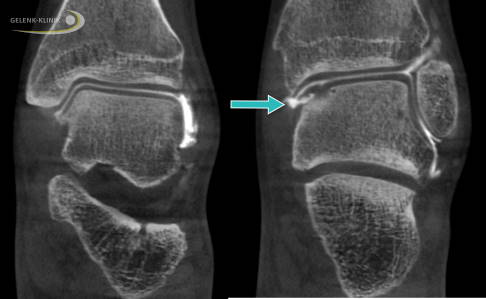

Hier sind verschiedene Ansätze in der Diagnostik sinnvoll. Der direkte Nachweis einer Schädigung der abdichtenden und dämpfenden Knorpelschicht kann nur im Rahmen einer invasiven Arthrografie erfolgen.

Hierbei wird die Gelenkschmiere mit einem jodhaltigen Kontrastmittel versetzt. Um die Verteilung der Gelenkschmiere genau darzustellen, benötigt man eine Darstellung mit Röntgenstrahlen ähnlich einer Computertomographie oder einer digitalen Volumentomographie (DVT). Letztere kann unter Belastung durchgeführt werden, womit sich zeitgleich eine Stellungsbeurteilung durchführen lässt.